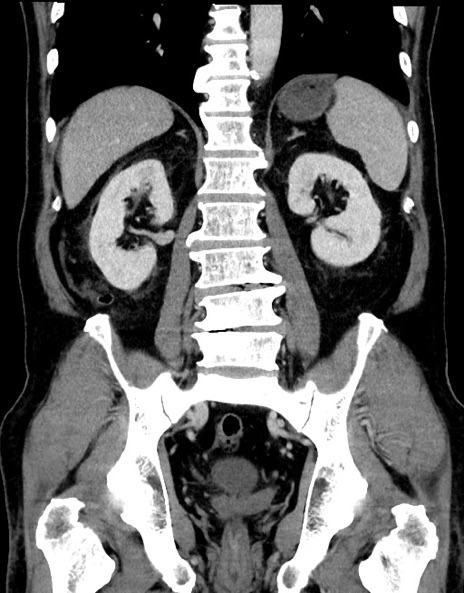

症例15(冠状断像)

【症例】70歳代男性

【主訴】腹痛

【現病歴】今朝から腹痛あり。全体的に痛い。特に左上の方。排ガスが今日はない。冷や汗が出る。

【既往歴】直腸癌術後

【身体所見】左側腹部〜上腹部に圧痛あり。腹膜刺激症状明らかなではない。軽度反跳痛。左下腹部に術後瘢痕あり。

【データ】WBC 7700、CRP 0.02